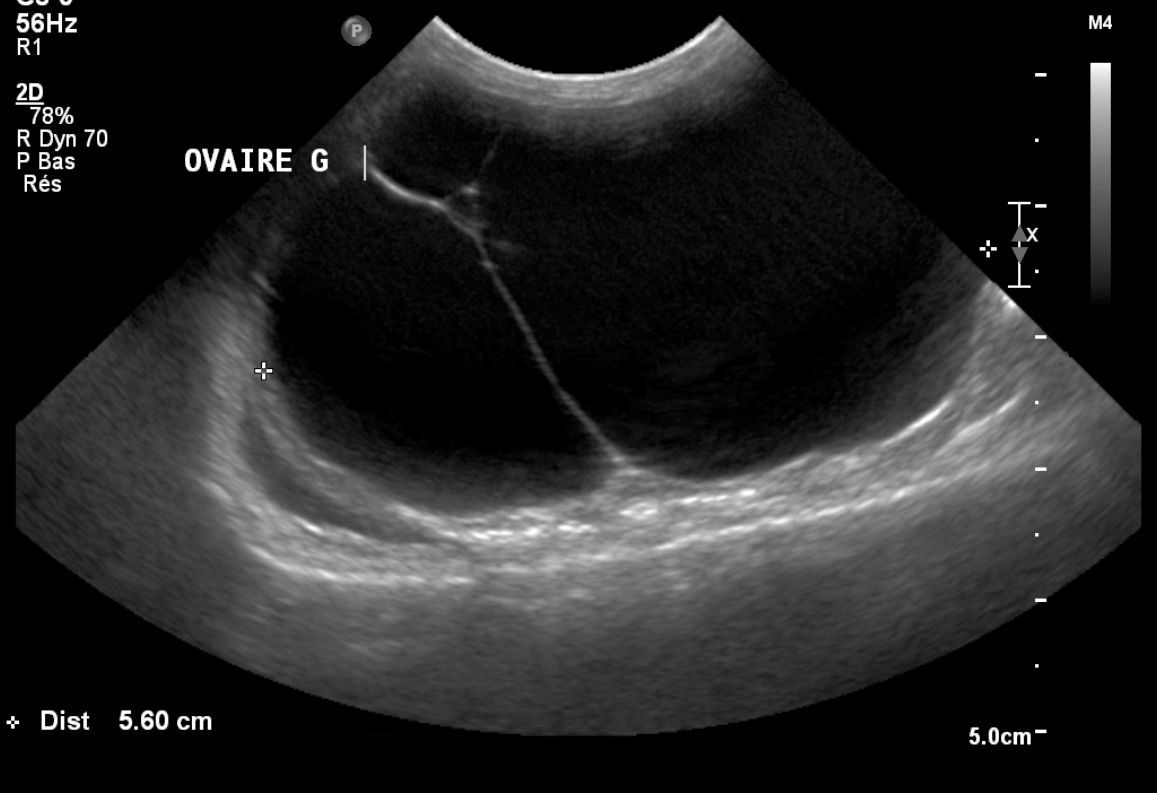

Kystes ovariens des cobayes

Les kystes ovariens sont très fréquents chez les femelles cobayes et gerbilles. La grande majorité du temps, ils sont totalement asymptomatiques. Mais parfois, du fait de leur taille, ils peuvent comprimer les organes abdominaux. Lorsqu'ils sécrètent des hormones, les kystes ovariens peuvent occasionner des pertes de poils importantes ou des tumeurs mammaires et utérines.

Le diagnostic se fait par échographie. Le traitement est chirurgical. Une technique d'ovariectomie par les flancs est généralement préférée en l'absence de tumeur utérine, elle est de bon pronostic.